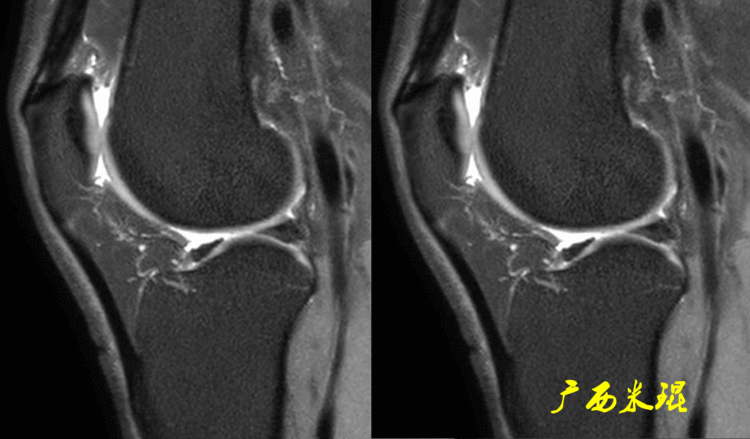

在MR上不论 看到的Ⅱ级信号范围多大,只要其没有与关节相通(必须是所有的截面)就不是半月板撕裂。下面的这张MR,内侧半月板后角退变较重,软骨尚好,如果我们把其他的截面阅看完,就知道只是半月板退变。

而下面的这张MR,内侧半月板后角退变较重,形态发生改变,软骨磨损重,相互之间对合差,如果我们把其他的截面阅看完,就知道这个病人的半月板发生撕裂。